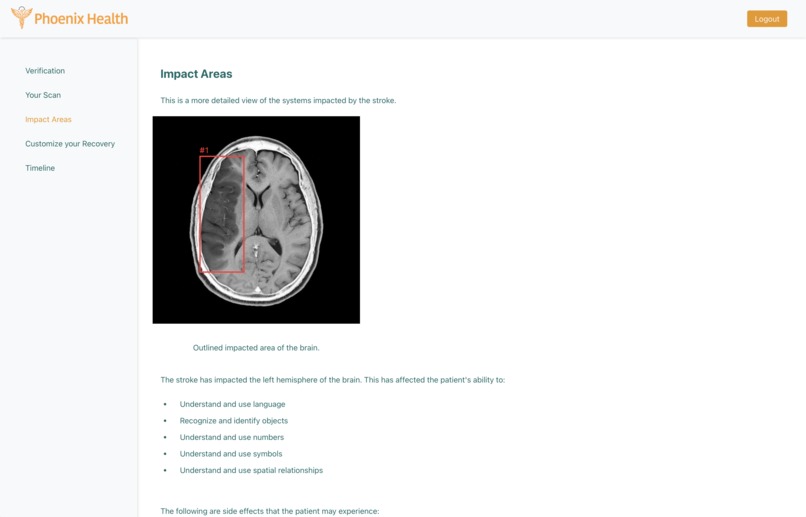

Phoenix Health seamlessly integrates with patients' existing medical records and MRI/CT scans. By obtaining permission from both the patient and the doctor, our service analyzes the latest MRI or CT scans and compares them to pre-stroke scans. This analysis facilitates the creation of a personalized, sustainable, and effective recovery strategy. Phoenix Health continues to monitor the patient's progress, allowing for real-time adjustments to the recovery plan as needed.